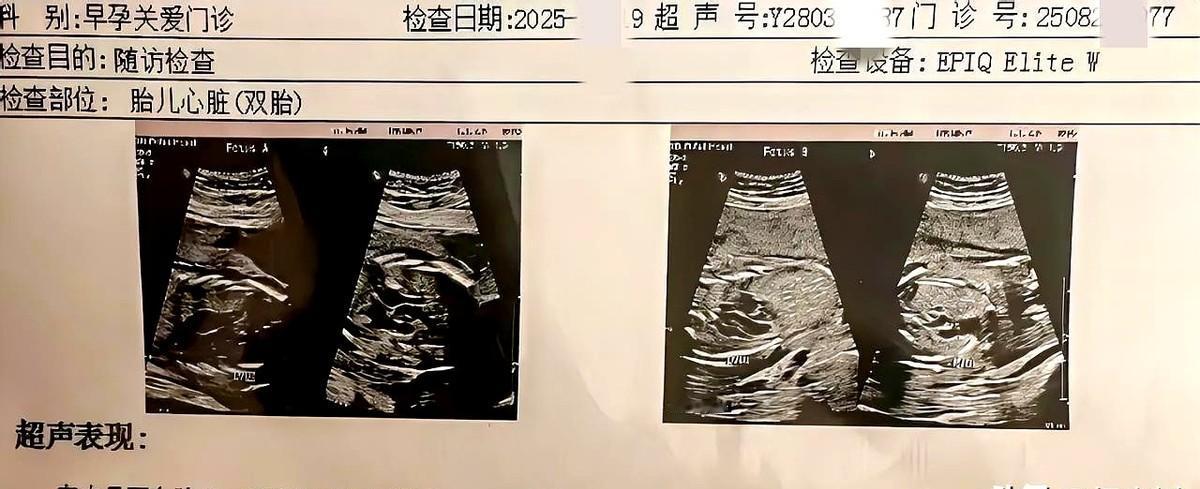

太意外了我老婆怀了双胞胎! 这次真的是意外怀孕了,我老婆已经44岁了,还是双胞胎! 这到底咋办呢? 还能不能够要这两娃啊! 现在老婆年龄也是高龄孕妇了,养两个小宝生活压力已经很大了。 有孩子就有财富,往后人和人最大的差距就是比谁的孩子多! 你多大福报能同时拥有两孩子,堕胎就是杀人! 真不怕因因果果! 希望珍惜这两孩子,这孩子是报恩来的! 有大福报! 这事谁说的都没用,还是要你家的当事人算算你家的经济条件,允许,你不用问我们,条件不允许别给自己找麻烦了,本来你家就两个孩子了,都要辛苦挣钱了,再是双胞胎又来两个孩子养起来可不容易,不累死人,也得熬死人。 一是看你媳妇身体状况,二是你自己经济条件允许吗? 有房有车,家有100万以上存款可以考虑生。 必须留住,多子多福,穷了穷养,富了富养,儿女是财富的源泉